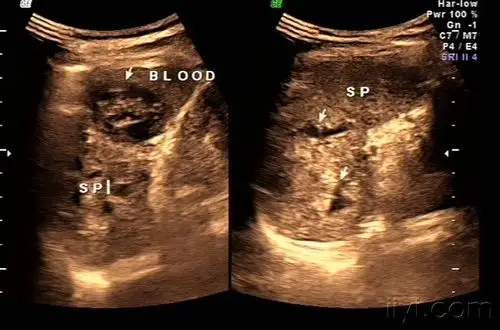

脾破裂——zengerya - 超声医学讨论版 - 爱爱医医学论坛